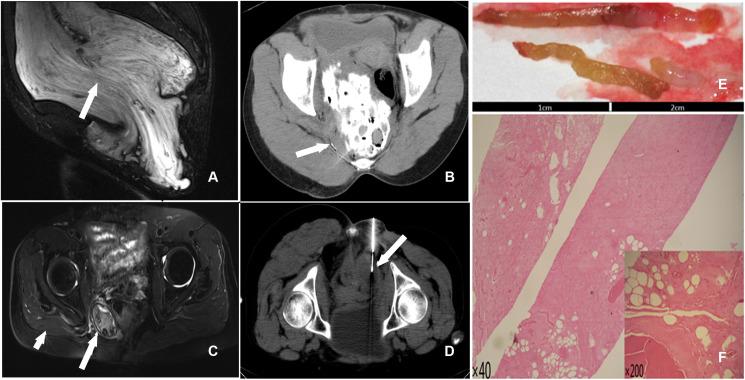

The maximum dimensions of the residual tumor were 12.6 cm and 14.0 cm. In one case, the lesion was in the pelvis and protruded into the vulva. Eighty milliliters of liquid with a mixture of glacial acetic acid, anhydrous ethanol, and iohexol (10:9:1) was used for chemical ablation therapy multipoint injections with a single needle. However, a pelvic fistula developed 1 month later. In another case, the lesion was located in the abdominal wall. The ablation procedure was improved by performing chemical ablation therapy with multiple needles for multi-point injections of smaller than 30 ml injections for each procedure. To date, no recurrence or metastasis has been observed in the two cases.

https://cdn.ncbi.nlm.nih.gov/pmc/blobs/627a/10061005/1243798edc00/fonc-13-1154283-g001.jpg